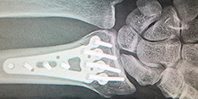

Согласно статистике, в 1-4% случаев возникает бактериальная инфекция после установки имплантата. А в случае сложного перелома риск развития инфекции повышается до 30%. Традиционно применяется антибиотическая терапия, чтобы справиться с этой проблемой. Но всегда есть риски, что инфекция станет устойчивой к антибиотикам или будет аллергия. Иногда даже требуется повторная операция.

Новый материал с наночастицами платины и железа за 8-12 часов уничтожает 98% окружающих его вредных бактерий. Ему под силу справиться со стафилококком, кишечной палочкой, клебсиеллой пневмонии. Что важно, иммунная система могла работать в нормальном режиме — лимфоциты не страдали. В ближайшее время должны быть проведены полноценные испытания на животных.